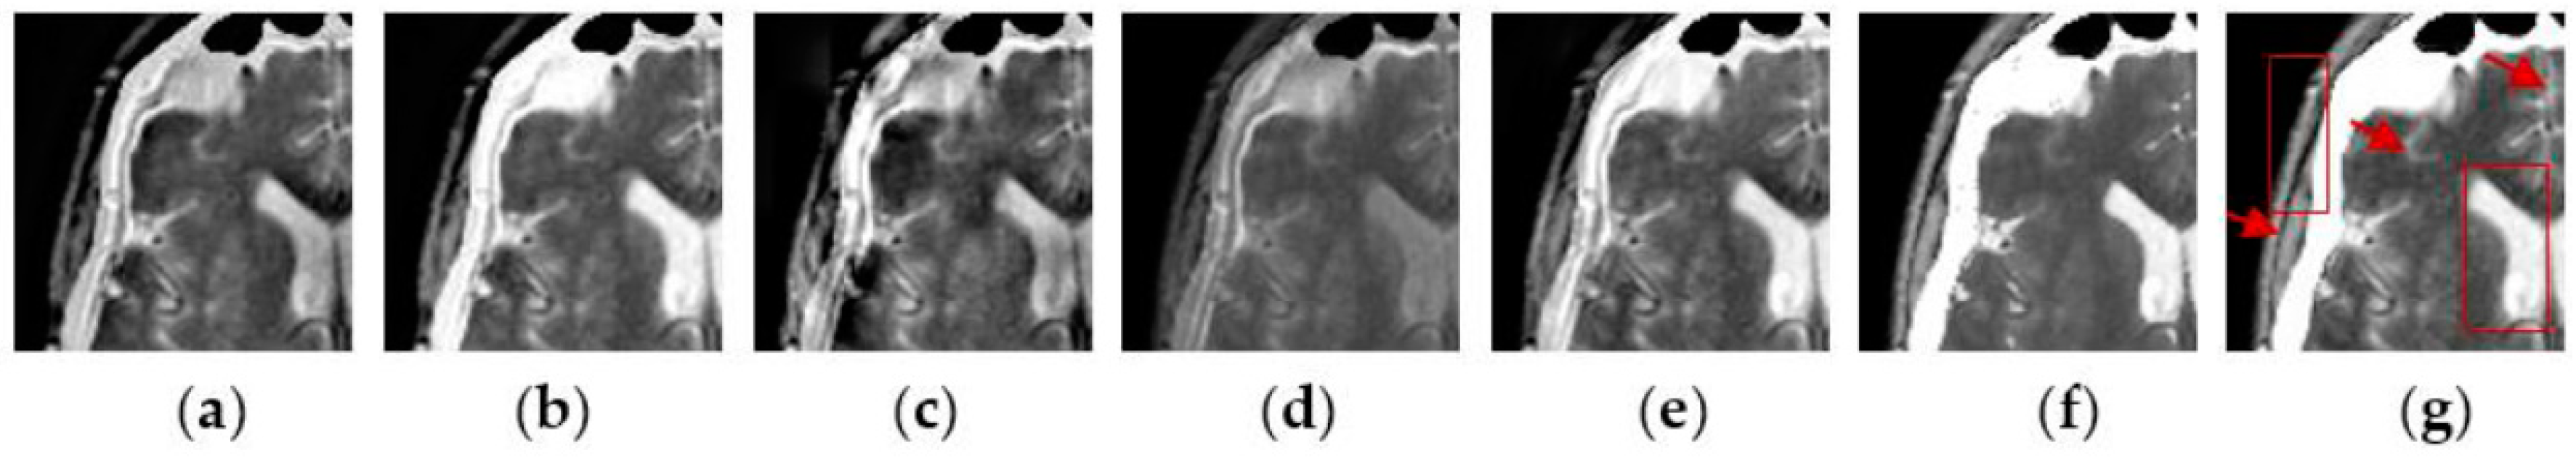

To further verify the advantage of the proposed SCM-M method in multimodal image fusion, Figure 11 and Figure 12 show the enlarged views of fused results for all evaluated methods operating on regions of interest (ROIs) denoted by the red boxes in Groups 1 and 6 in Figure 6, respectively. Figure 13 shows the enlarged views of fused results for the proposed method, the m-PCNN method and the SCM-F method operating on ROIs denoted by the red boxes in Groups 7 and 8 shown in Figure 6. In Figure 11 and Figure 12, we can see that the SCM-M method can maintain the salient information in the source images and provide better visual perception with less loss in luminance or contrast than other compared methods. To explain this point better, some edges and regions have been chosen from Figure 11g and Figure 12g. It can be seen from Figure 11 that the SCM-M method can provide better edge preservation than all other methods as pointed by the three red arrows. Meanwhile, compared with the DWT, NSCT and NSCT-SR methods, the SCM-M method can maintain the information in the MR image shown in Figure 6f better without introducing artifacts as indicated by the two red boxes. In Figure 12, we can see that the proposed method can keep the integrity of the edge marked by the red arrow best among all evaluated methods. Likewise, as pointed by the green arrow, the edge can be preserved very well by the proposed method while it has been damaged very seriously by other methods. Besides, the sharpness of the region shown by the red box can be maintained by the proposed method better than by the compared method. Furthermore, it can be seen in Figure 13 that compared with the m-PCNN and SCM-F methods, the SCM-M method can preserve fine image details and maintain image contrast better.

Figure 11.

Enlarged views of fused results of ROIs denoted by the red boxes in Group 1 in Figure 6 for the seven methods: (a) the DWT method; (b) the NSCT method; (c) the NSCT-SR method; (d) the m-PCNN method; (e) the PCNN-NSCT method; (f) the SCM-F method; and (g) the SCM-M method.

Figure 12.

Enlarged views of fused results of ROIs denoted by the red boxes in Group 6 in Figure 6 for the seven methods: (a) the DWT method; (b) the NSCT method; (c) the NSCT-SR method; (d) the m-PCNN method; (e) the PCNN-NSCT method; (f) the SCM-F method; and (g) the SCM-M method.